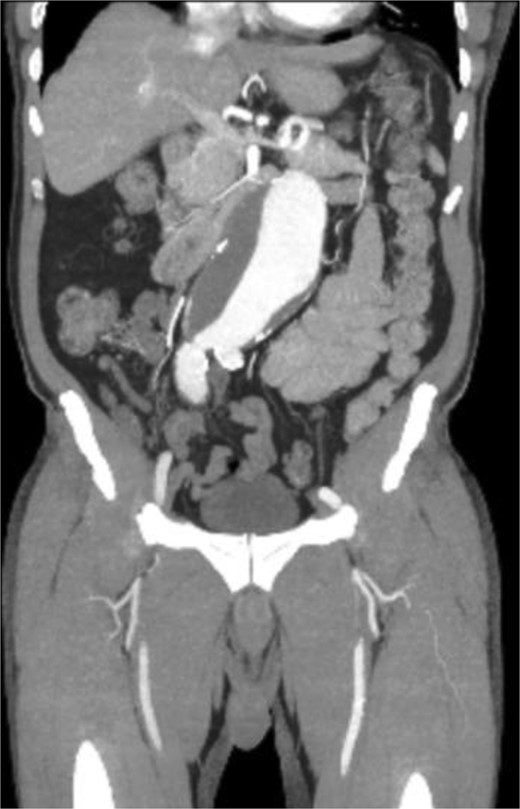

A 71-year-old male with a past medical history of hypertension, dyslipidemia, and renal insufficiency presented to the emergency department with headache and dizziness that began after performing manual labor. The only abnormality with initial vital signs was an elevated blood pressure. Physical exam revealed a palpable pulsatile mass in the epigastrium. An electrocardiogram showed normal sinus rhythm with signs of previous inferior and anterolateral infarcts. Troponin levels were within normal limits. Further workup with an echocardiogram demonstrated left ventricular hypertrophy and ejection fraction (EF) of less than 50%. Due to the pulsatile abdominal mass, a computed tomography (CT) of the abdomen without contrast, and subsequent CT angiogram of the abdomen and pelvis, was completed that demonstrated a 7.1-cm infrarenal AAA with a large mural thrombus causing luminal narrowing (Figs 1 and 2).

CT angiogram of abdominal aorta and iliofemoral artery coronal view.